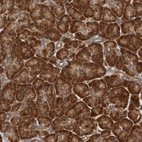

Immunohistochemical staining of human tonsil shows strong cytoplasmic positivity in non-germinal center cells.